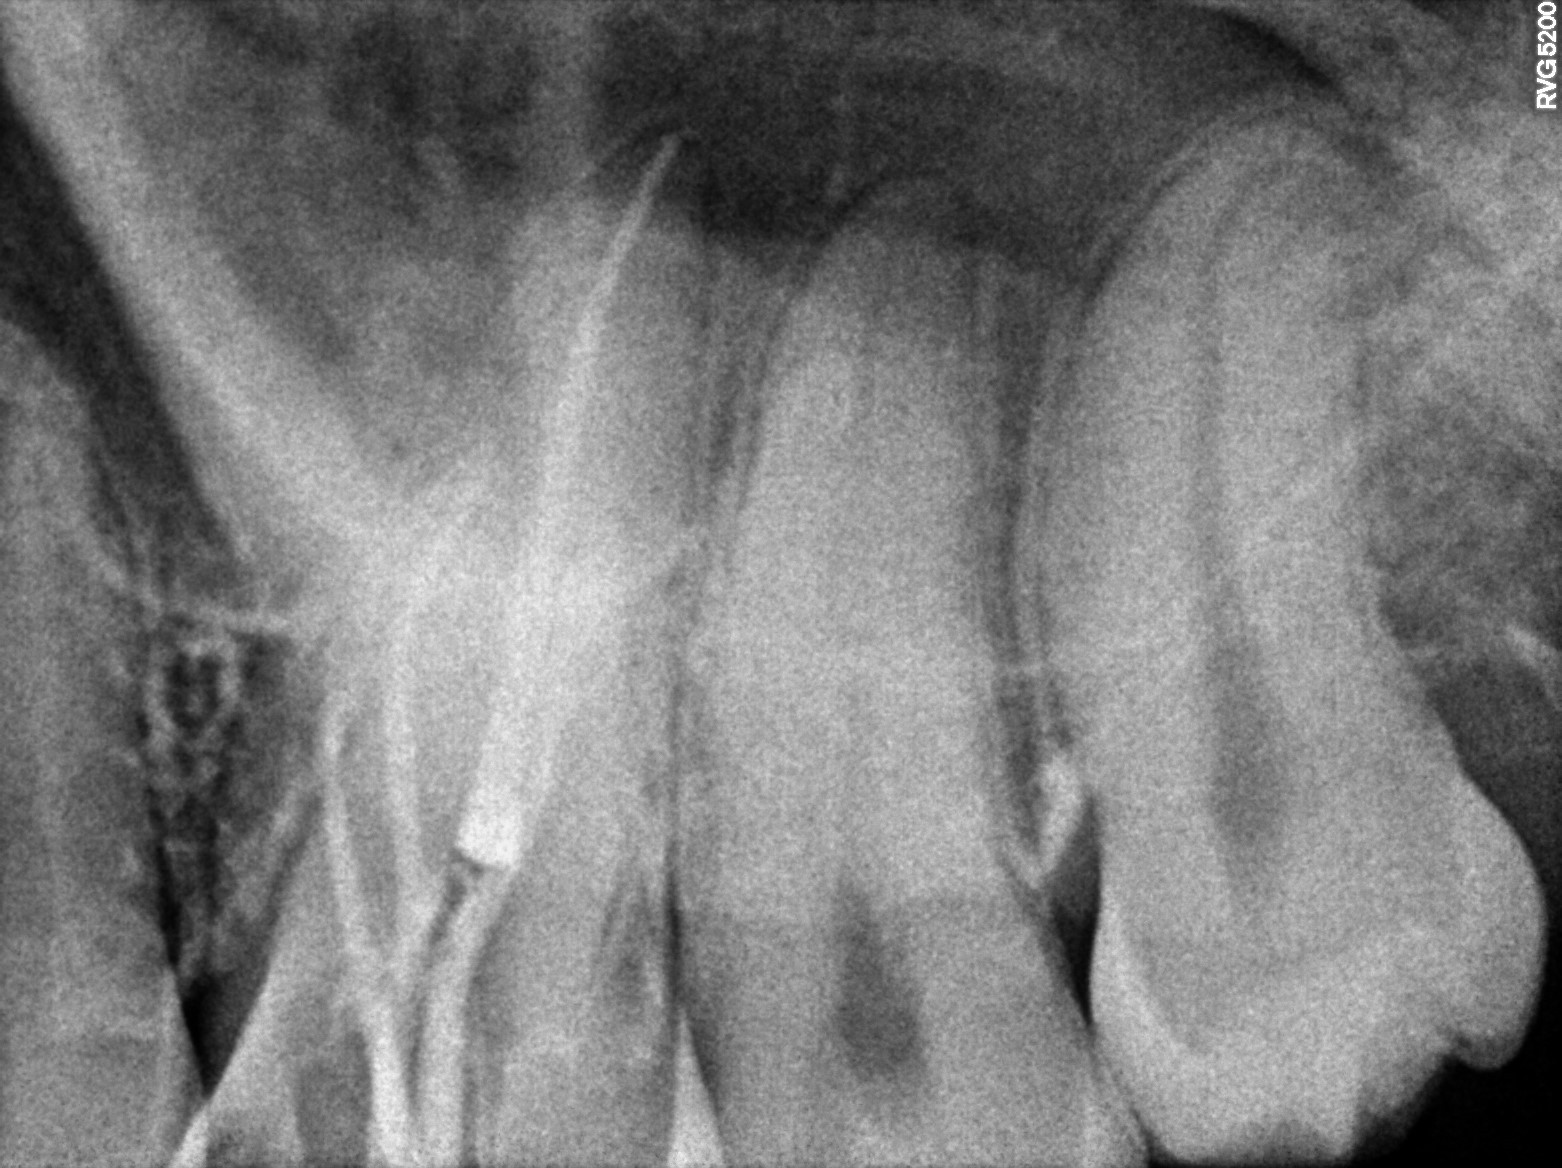

Dental Radiographs FHIR: DocumentReference · LOINC 24641-7

xray_1773645310_0.jpg

24641-7

| Dental pulp necrosis | — | 234946006 | resolved | 2026-03-13 | a/o 26 pl 25.06 1 stopper, db 25.5 1.5 stopper, mb2 20.04 3 stopper, mb short |

| Root canal treatment | 234780006 | D3320 Endodontic therapy, premolar tooth | ##26, #25 | 2026-03-13 | completed | a/o 26 pl 25.06 1 stopper, db 25.5 1.5 stopper, mb2 20.04 3 stopper, mb short |

| 2026-03-13 13:02 | fulfilled | a/o 26 pl 25.06 1 stopper, db 25.5 1.5 stopper, mb2 20.04 3 stopper, mb short — Dr Riyaz |